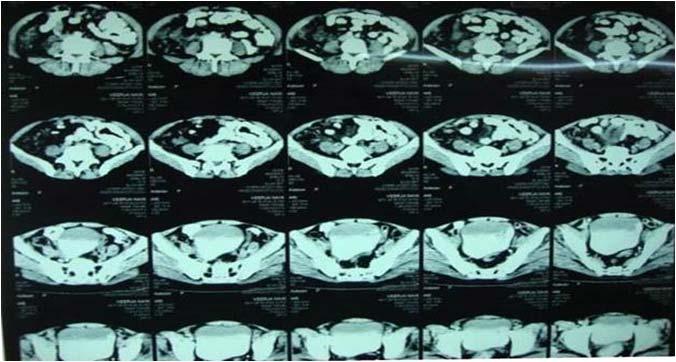

Radiological imaging was done in all the cases. USG findings revealed solitary masses in 45 cases (80.35%) and diffuse masses in 11 (19.64%). Solitary masses were around 45 in number out of which 30 were diagnosed as HCC. Right lobe had around 30 (66.7%) whereas left lobe had 15 (33.33%) masses respectively. Maximum (SOL’s) observed showed hyper-echogenicity present in 43 cases (76.78%). Heterogenous echotexture was observed in 6 cases (10.71%) (Fig 1).

CT scan was done in two patients which showed multiple well defined hyperdense lesions and hypodense lesions in another patient. Cyto-radiological correlation of hepatic masses was seen in 94% cases (Fig 2).

Fig 1 — USG liver showing well defined heteroechoic lesion in left lobe

Fig 2 — CT liver showing multiple enhancing focal hepatic lesions suggestive of metastasis